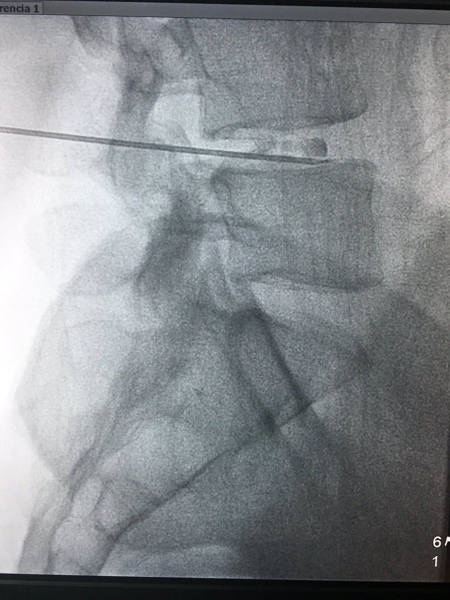

La técnica quirúrgica es relativamente sencilla, con anestesia local y sedación se introduce una aguja en el disco intervertebral. El paciente se coloca boca abajo, para tener control de por dónde va la aguja debemos utilizar un aparato de rayos X. Una vez que comprobamos que la aguja está correctamente situada inyectaremos el Discogel, gracias al tugsteno y al aparato de rayos X tendremos visión directa sobre lo que ocurre en cada momento.

Imágenes

Imágen radiogáfica inyeccion Discogel